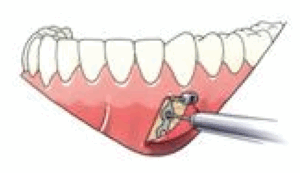

De platen zijn stevig bevestigd met 2 (in de onderkaak) of 3 (in de bovenkaak) schroeven op een veilige afstand van de wortels van de tanden. Meestal worden de bovenste platen met monocorticale schroeven, 2,0mm diameter en 5mm lengte voor de onderste schroeven en 7mm lengte voor de bovenste schroef op de infra-zygomatische top van de bovenkaak gestoken. In de onderkaak worden de platen meestal tussen de hoektand en de laterale snijtand geplaatst. Voor sommige indicaties kunnen ze ook tussen de eerste molaar en de tweede bicuspide worden geplaatst.

Bestaat uit een miniplate met 2 of 3 gaten, een verbindingsstang en een bevestigingseenheid met een blokkeerschroef. Het ontwerp van de cilindrische bevestigingseenheid maakt het mogelijk om allerlei soorten draden te bevestigen om verbinding te maken met het vaste apparaat.